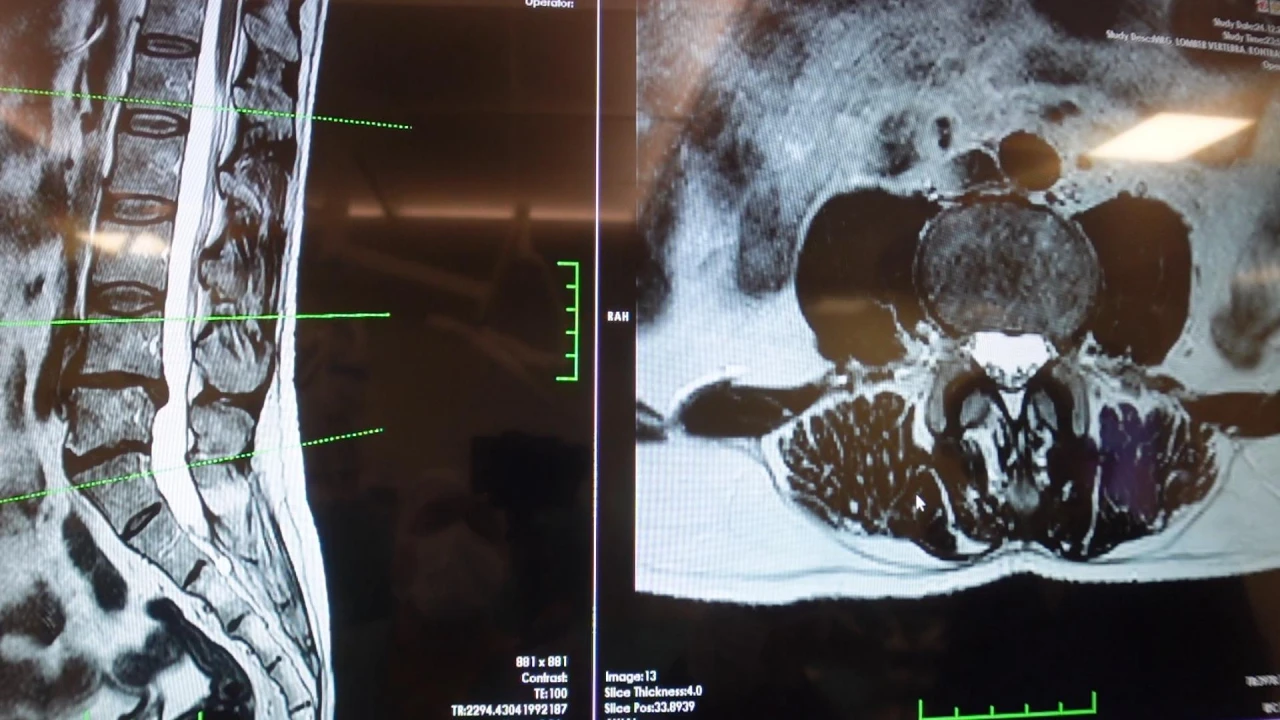

Bir diğer önemli hasta grubunun ise omurilik kanal darlığı olan hastalar olduğunu ifade eden Prof. Dr. Erol, dejeneratif süreçler sonucunda omurilik kanalında ve sinir köklerinin geçtiği alanlarda daralma ve kireçlenme meydana geldiğini söyledi.

Bu durumun sinirlerde sıkışmaya yol açtığını belirten Erol, hastaların özellikle ayakta dururken veya yürürken bel, kalça ve bacaklara yayılan ağrılar hissettiğini, yürüyüş mesafesi arttıkça oturup dinlenme ihtiyacı duyduklarını aktardı.